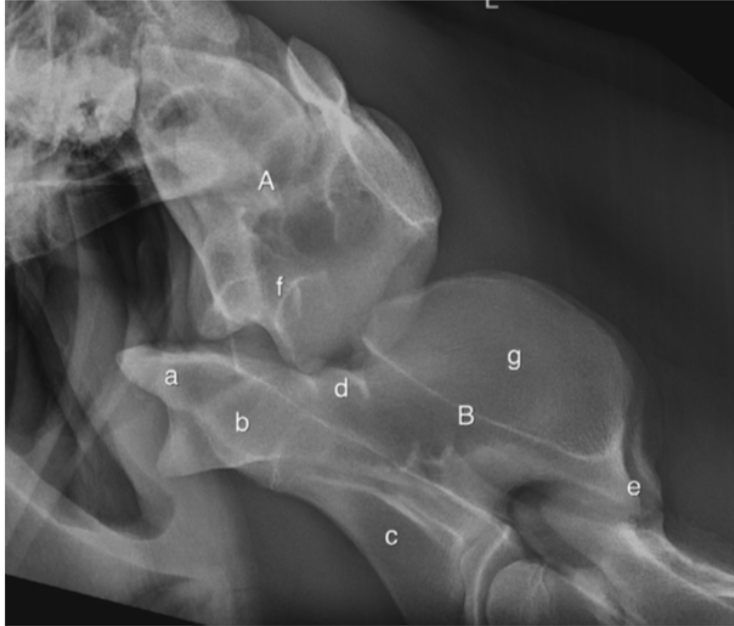

What is the diagnosis?

Label the diagram

Complete ventral luxation of the dens

A - Atlas

B - Axis

a - odontoid process

b - Body of C2 - cranial

c - Vertebral body of C2, caudal

d - vertebral canal

e - caudal AP of C2

f - concavity of atlas where dens usually site

g - C2 DSP

Dens physis is closed so >8mo but cranial physis of C3 open so <2yrs